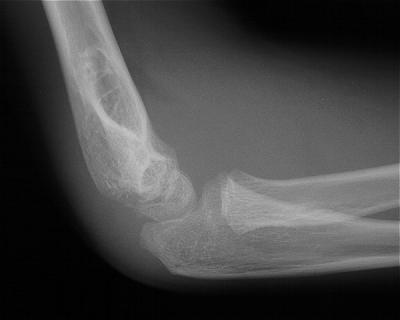

Initial injury: supracondylar fracture in a 9 year old:

Five years later, he has limited motion (E/F 35/100) and painful clicking with elbow flexion and extension.

Plain films show humeral osteophytes and posttraumatic changes of the capitellum and radial head.